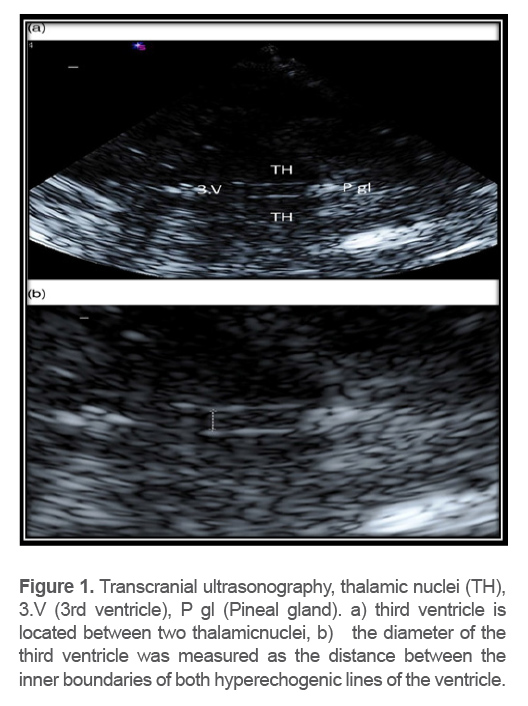

TCS was performed by an experience dneur ologist using a 2 MHz phased array transducer. Next, a transtemporal window inthe axial imaging plane was used. The width of the third ventricle was assessed at the thalamus level and measured as the distance of the leading edges of the brain-ventricle interfaces in axial image planes (Figure 1).

Figure 1. Transcranial ultrasonography, thalamic nuclei (TH), 3.V (3rd ventricle), P gl (Pineal gland). a) third ventricle is located between two thalamicnuclei, b)   the diameter of the third ventricle was measured as the distance between the inner boundaries of both hyperechogenic lines of the ventricle.